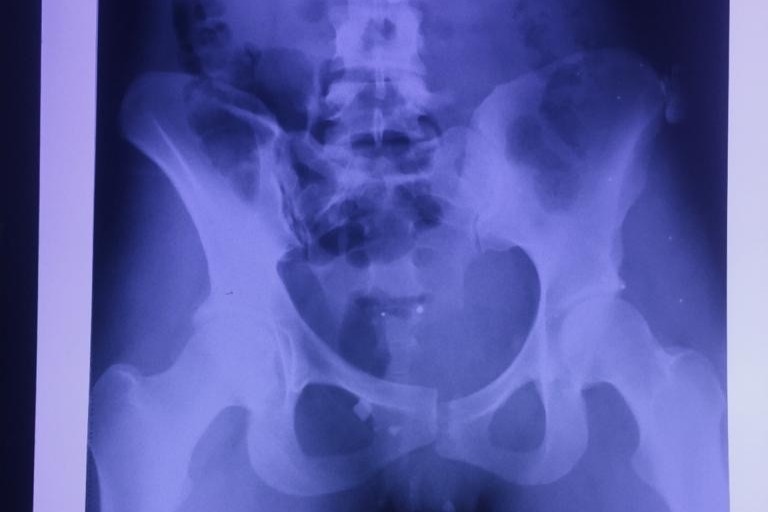

Long story short, the details are sad and boring, my left hip was broken, my pelvis was broken and I have an 8 cm open wound around my pelvic area. Immediately after the accident, I had to have emergency surgery in which they applied a fixator (a metal stick attached to my hip/pelvis to keep it attached to hold it in place with a rod inside and coming outside of my body). Due to the shitty position of the fixator and wound they had to perform a temporary ileostomy, in a few words, let’s just say toilet paper is a very precious item which I won’t be needing for a while.

It will take me around 12 weeks to fully recover and to be able to walk again. I left hospital 3-weeks after the accident with a total bill of 55.000 $. In order to recover I will need two more surgeries and for safety issues they must be performed separately, one to remove the fixator and replace it with an internal plate, and another one to take off the ileostomy. I expect the total cost will be around 30.000$ for both procedures.